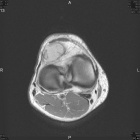

Patient is a 45 y/o Ortho nurse who presented w/ enlarging painful R. knee mass for past year; PMH: ovarian cysts s/p rupture

PE: R. knee w/ well circumscribed mass at the lat. aspect of the patella; + tenderness to palpation; normal PROM; NVI

Zoom image: Radiological image Radiological image.